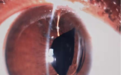

患者侯某,女,49岁,2年前在外院做了双眼白内障联合人工晶体植入术。7天前无任何诱因患者突感右眼视力下降,来到西安市第一医院眼科马挺主任门诊就诊,原来是她右眼的人工晶体出现了脱位、移位(见下图1-2),视力已下降至0.15,患者及家属十分焦急。

图1